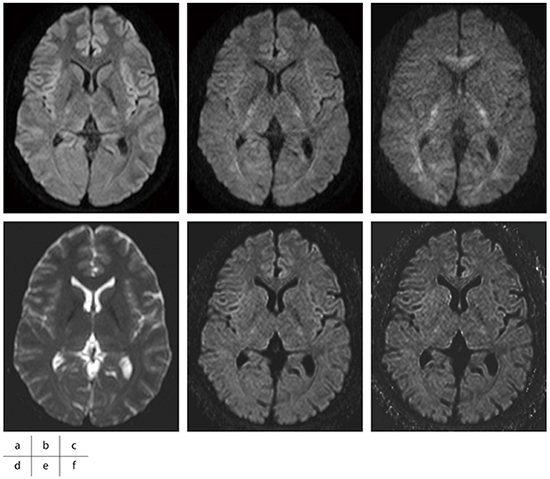

aDWIではb値を大きくするほどSNRの低下,歪みが強くなるといったデメリットがあるが,cDWIではSNRを担保しつつ,歪みにも影響しない(図4)。また,cDWIは後処理のみで作成が可能なため,追加撮像や加算回数を増加させる必要もなく,患者に負担をかけずに病巣の検出能向上に用いることができる。非常に実用的な画像処理であり,早期の診断へつなげるため,今後も積極的な作成を考えている。

図4 aDWIのSNR,歪みの比較

a:aDWI=1000s/mm2

b:aDWI=2000s/mm2

c:aDWI=3000s/mm2

d:aDWI=0s/mm2

e:cDWI=2000s/mm2

f:cDWI=3000s/mm2